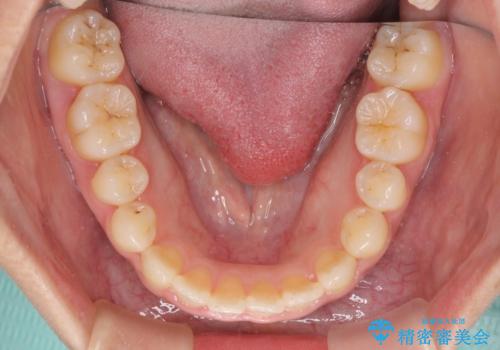

1年半はかかると思っていた治療期間ですが、反対咬合となっている前歯が思いの外早く動き、僅か9ヶ月で終了させることができました。

前歯を気にせず笑えるようになり、患者様には大変満足していただきました。